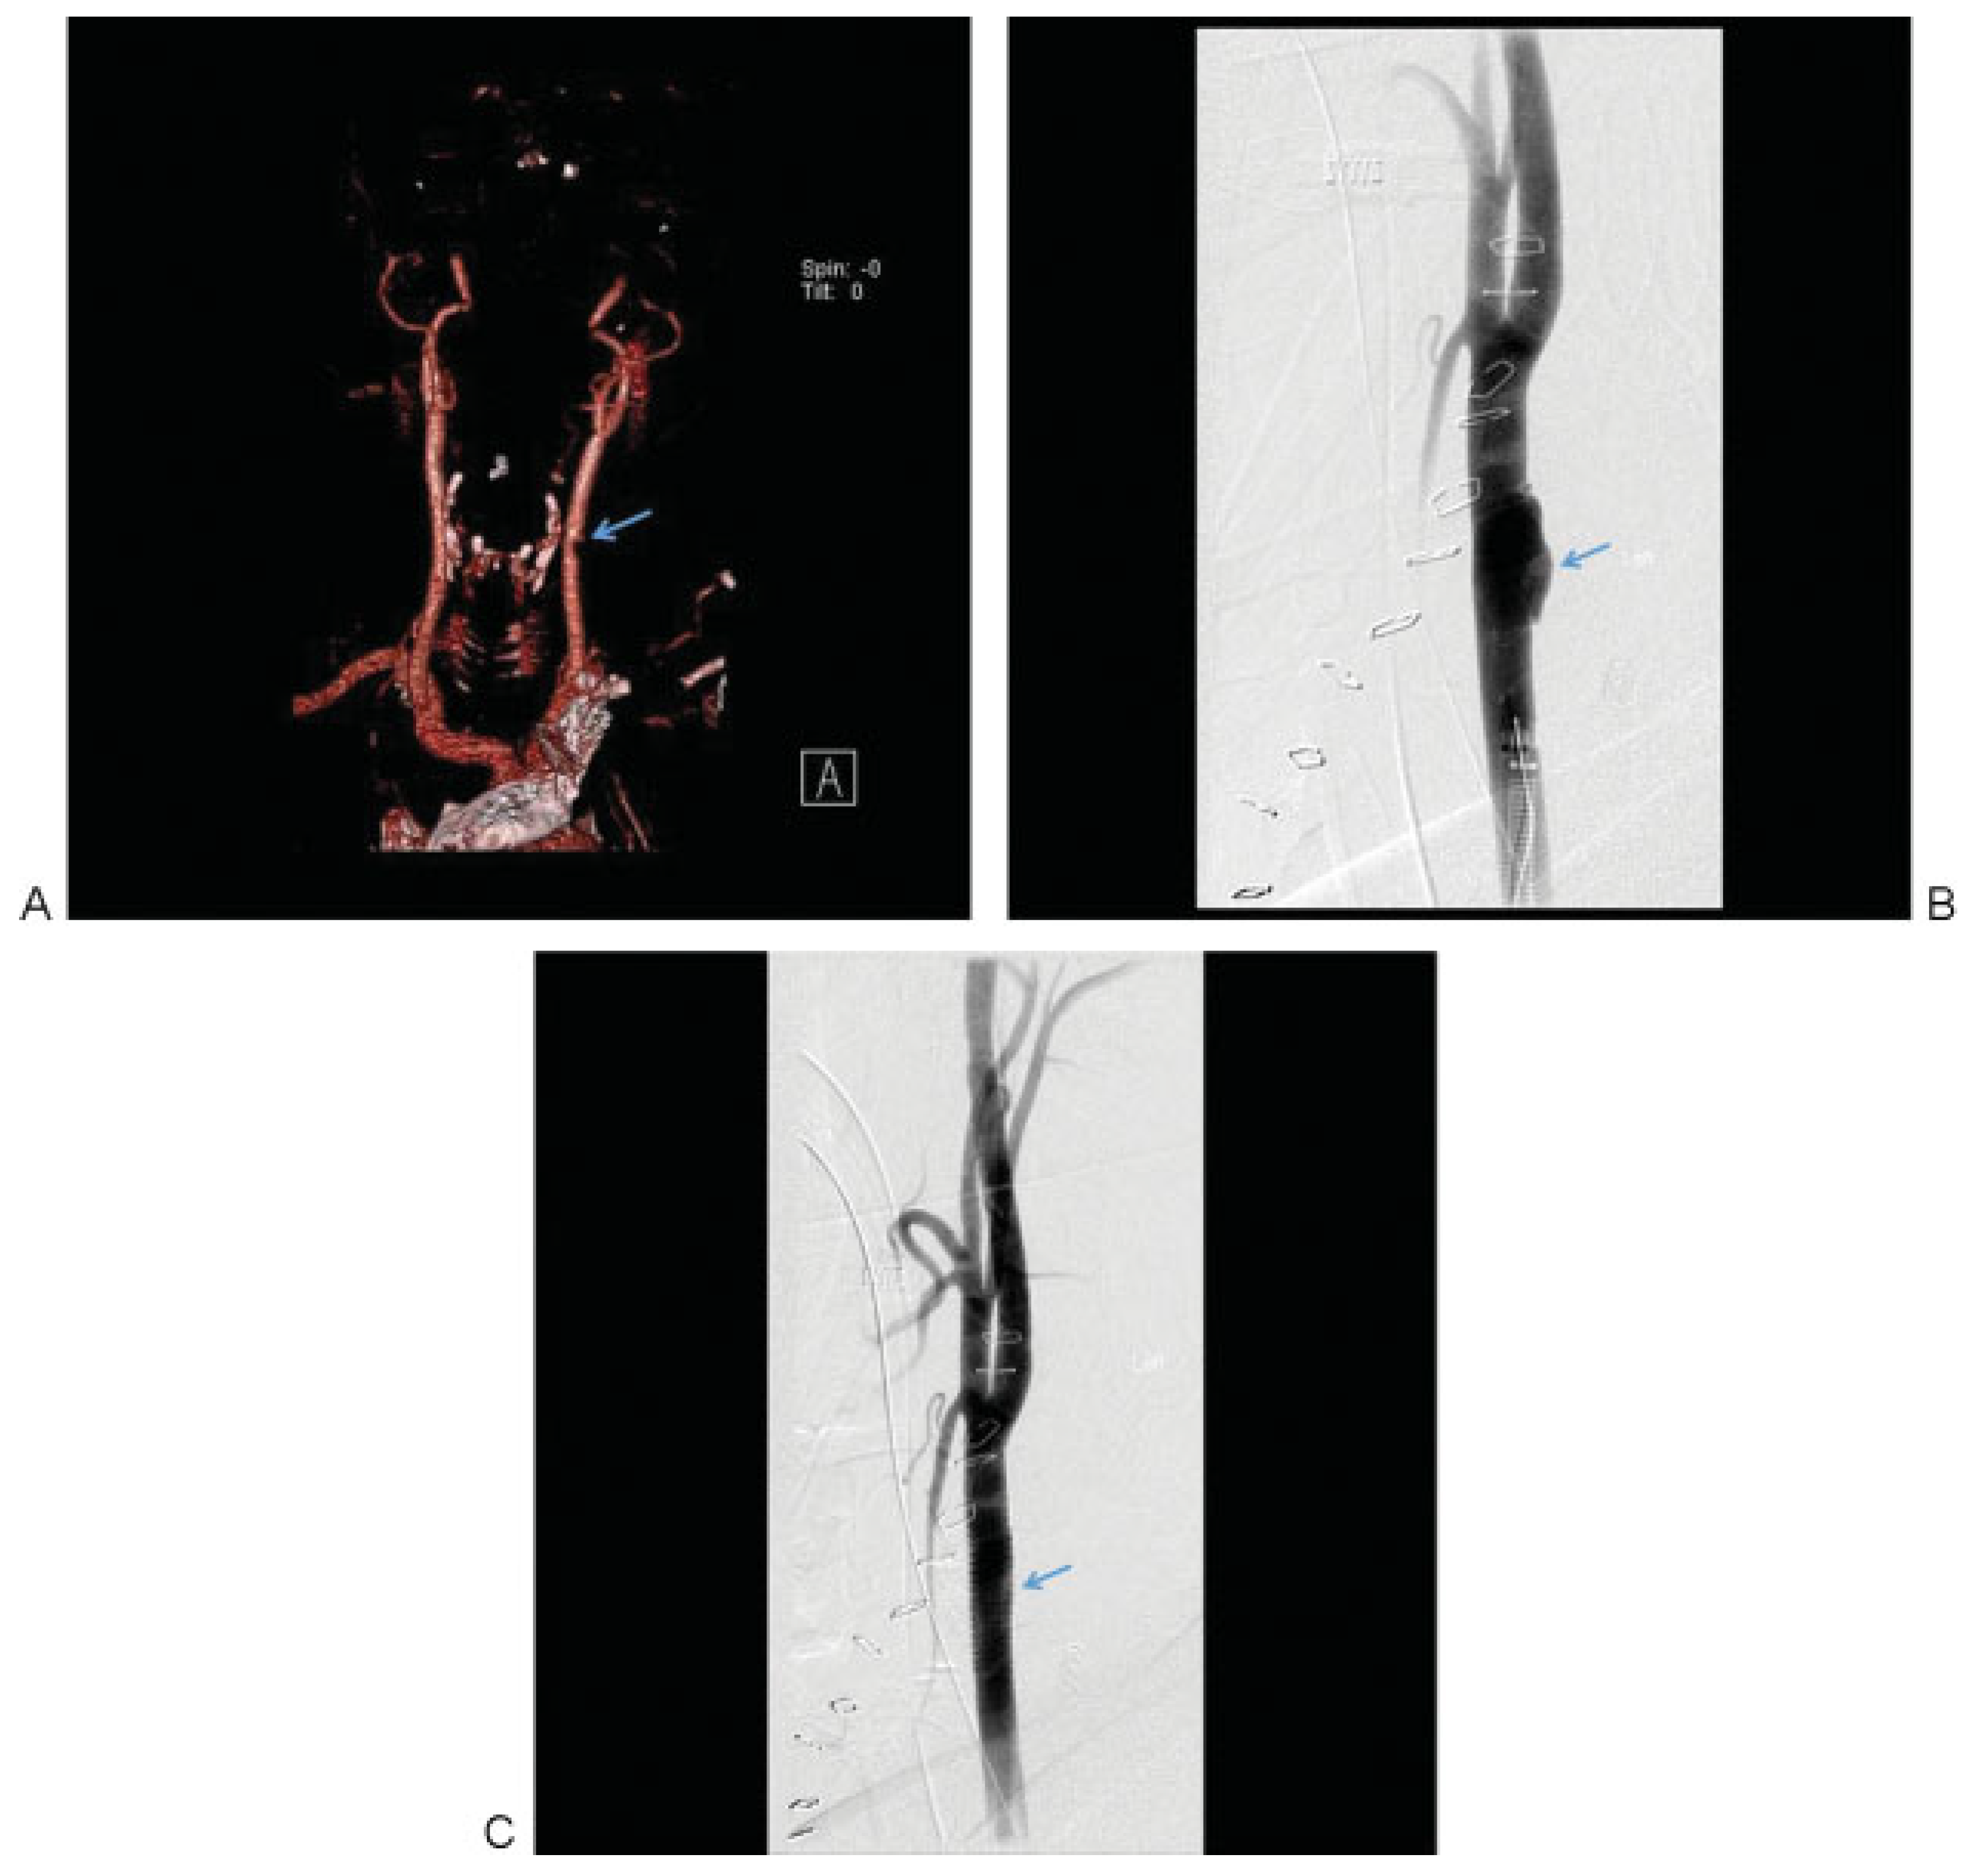

Penetrating Extracranial Carotid Artery Trauma

Intracranial Carotid Artery Trauma